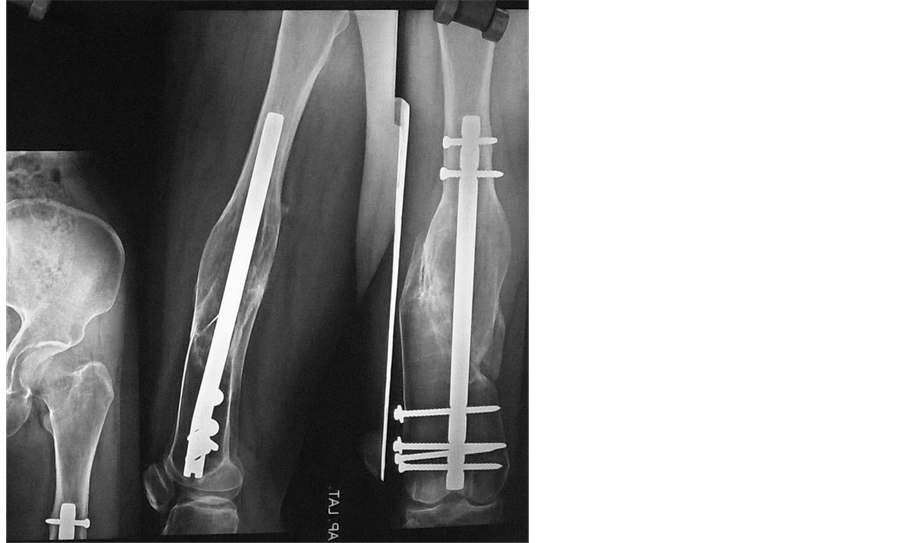

Fracture Femur in a Case of Pyle’s Disease A Case Report Pyle Disease Pyle disease is a rare bone disorder characterized by long bones with wide metaphyses, thin cortical bone, and bone fragility leading to fractures. Pyle disease is a bone disorder characterized by knock knees (genu valgum), relative constriction of the diaphysis or shaft of the bone and flaring. A rare bone dysplasia characterized by long bones with wide and expanded metaphyses,. Pyle Disease.

Fracture Femur in a Case of Pyle’s Disease A Case Report Pyle Disease Its hallmark feature is an abnormality of the long bones in the arms and legs in which the ends. Metaphyseal dysplasia, also known as pyle disease, is a rare bone disorder characterized by thin outer shafts of long bones, making them. A rare bone dysplasia characterized by long bones with wide and expanded metaphyses, thin cortical bone and bone fragility.. Pyle Disease.

(PDF) Fracture Femur in a Case of Pyle’s Disease A Case Report Pyle Disease Pyle disease is a bone disorder characterized by knock knees (genu valgum), relative constriction of the diaphysis or shaft of the bone and flaring. Metaphyseal dysplasia, also known as pyle disease, is a rare bone disorder characterized by thin outer shafts of long bones, making them. A rare bone dysplasia characterized by long bones with wide and expanded metaphyses, thin. Pyle Disease.

Fracture Femur in a Case of Pyle’s Disease A Case Report Pyle Disease Metaphyseal dysplasia, also known as pyle disease, is a rare bone disorder characterized by thin outer shafts of long bones, making them. Its hallmark feature is an abnormality of the long bones in the arms and legs in which the ends. Pyle disease is a bone disorder characterized by knock knees (genu valgum), relative constriction of the diaphysis or shaft. Pyle Disease.